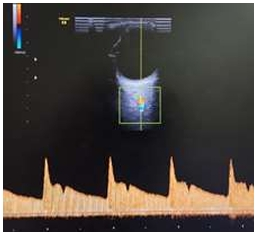

Assinale a alternativa CORRETA que representa a imagem de maior risco para pré-eclâmpsia, considerando as

pacientes com mesmo quadro clínico e obstétrico.